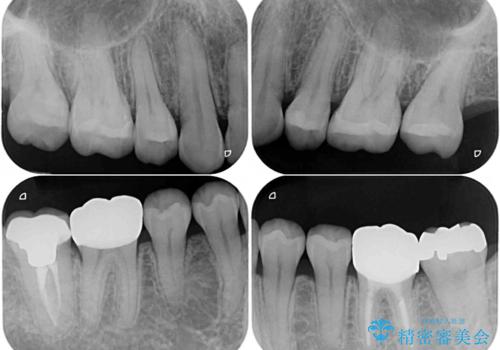

- 以前行った抜歯矯正が後戻りし、開いてしまったスペースが気になるとのことで来院された患者様です。

インビザラインを用いて開いてしまったスペースと前歯のデコボコを改善することとしました。

矯正治療後には気になっていた銀歯をセラミッククラウンやセラミックインレーにて治療することとしました。

上顎前歯を左右対称となるように歯列を整えたいとのことでしたが、すり減って形態が大きく異なっていたため、できる範囲での仕上がりとなりました。